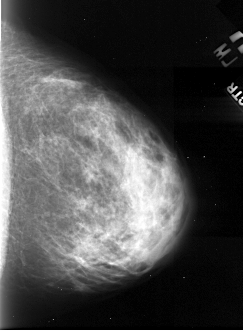

A_1103_1.RIGHT_MLO

RIGHT_MLO LINES 5206 PIXELS_PER_LINE 2986 BITS_PER_PIXEL 16 RESOLUTION 42 NON_OVERLAY